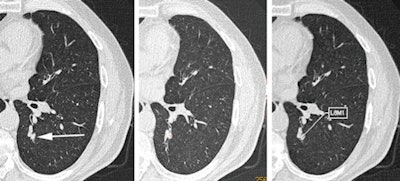

Dr. Mingzhu Liang, Dr. Wei Tang, and colleagues from Peking Union Medical College and Dr. David Yankelevitz, Dr. Claudia Henschke, PhD, and others from Mt. Sinai identified 50 lung cancers from the I-ELCAP study, found in patients recruited between 1994 and 2013. The tumors were missed on an initial lung screening exam (time 0), but they were visualized on subsequent screening exams (time 1).

Radiologists going back to time 0 were able to see them at that time as well. All cases had pathologic confirmation and 44 underwent surgical resection, the authors wrote.

In every case, CAD detected most of the missed nodules. Among the 50 cancers missed by the radiologist at time 0, the four CAD systems detected 56% to 70%. At time 1, the detection rates ranged from 74% to 82%.

All cancers were smaller at time 0 (average, 4.8 mm) and had grown by time 1 (average, 11.4 mm), "which suggested that size was a determining factor in the performance of the human reader," the group wrote.